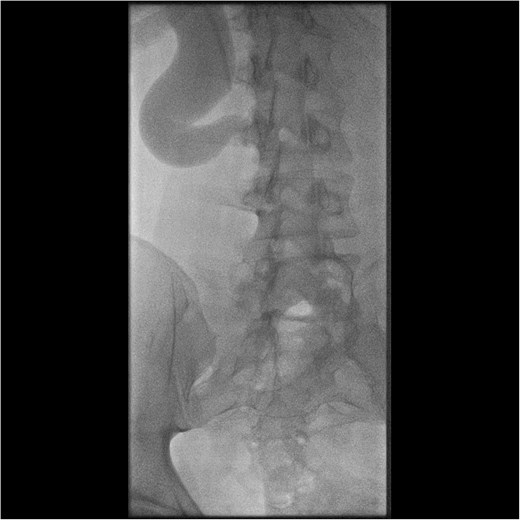

Initial work-up revealed microscopic haematuria and a mildly elevated creatinine of 156 μmol/L (65.4–119.3 μmol/L). A computerized tomogram (CT) urogram showed proximal hydroureteronephrosis with preserved renal cortex (Fig. 1). A diethylenetriamine pentaacetate (DTPA) renogram with diuretic showed accumulation of contrast then prompt excretion with administration of diuretic, suggesting partial obstruction or hypotonic collecting system (Fig. 2). At this point alternative diagnoses were considered, including RU. Ongoing severe right flank pain was noted despite multimodal analgesia and a right-sided nephrostomy was placed with immediate relief of pain and obstruction. Figure 3 shows the nephrostogram with S-shaped hydroureter. No further analgesia was required, and creatinine normalized (90 μmol/L). The case was discussed at a multidisciplinary meeting, wherein a unanimous diagnosis of RU was confirmed, and a plan for minimally invasive laparoscopic dissection and re-anastomosis of the ureter was made.

DTPA scan showing partially obstructed or hypotonic right kidney with resolution of obstruction following diuretic.